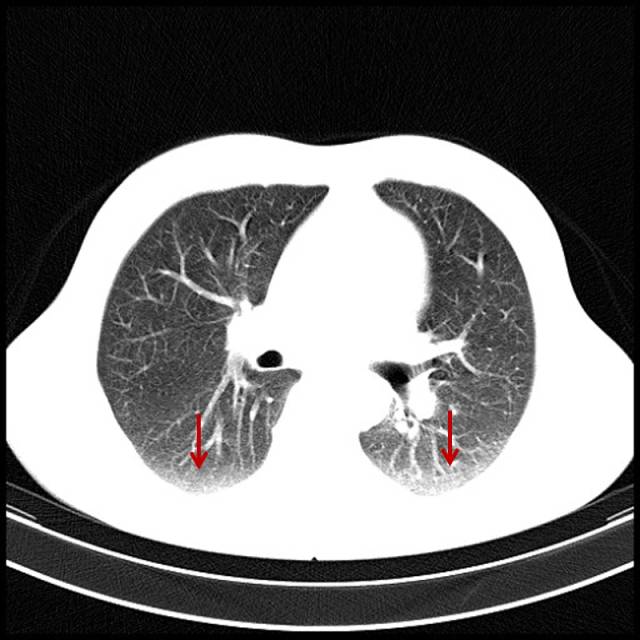

■吸烟导致双肺坠积效应

男,47岁,吸烟者,每天2盒。